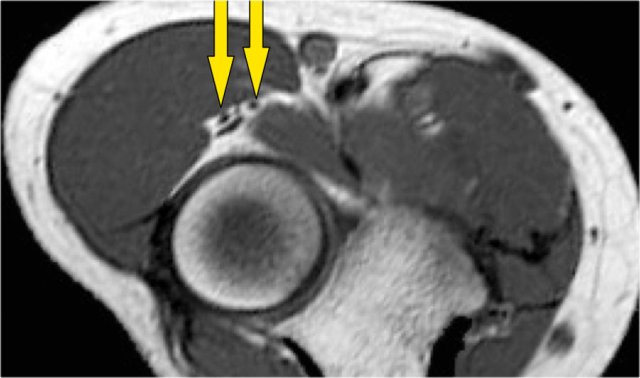

Here a different patient.

Notice that it is a young patient, because the physis is still open.

There is a large osteochondral lesion in the lateral trochlea (yellow arrows).

Notice the edema in the subchondral bone (red arrow).

The cartilage is still intact.